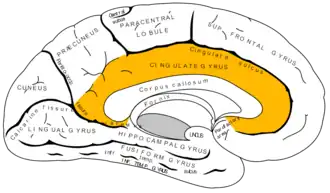

Medial surface of left cerebral hemisphere. (Isthmus labeled at left center.) | |

The cingulate gyrus commences below the rostrum of the corpus callosum, curves around in front of the genu, extends along the upper surface of the body, and finally turns downward behind the splenium, where it is connected by a narrow isthmus with the parahippocampal gyrus.

Medial surface of cerebral cortex - gyri

Isthmus of the cingulate gyrus, medial surface of right hemisphere